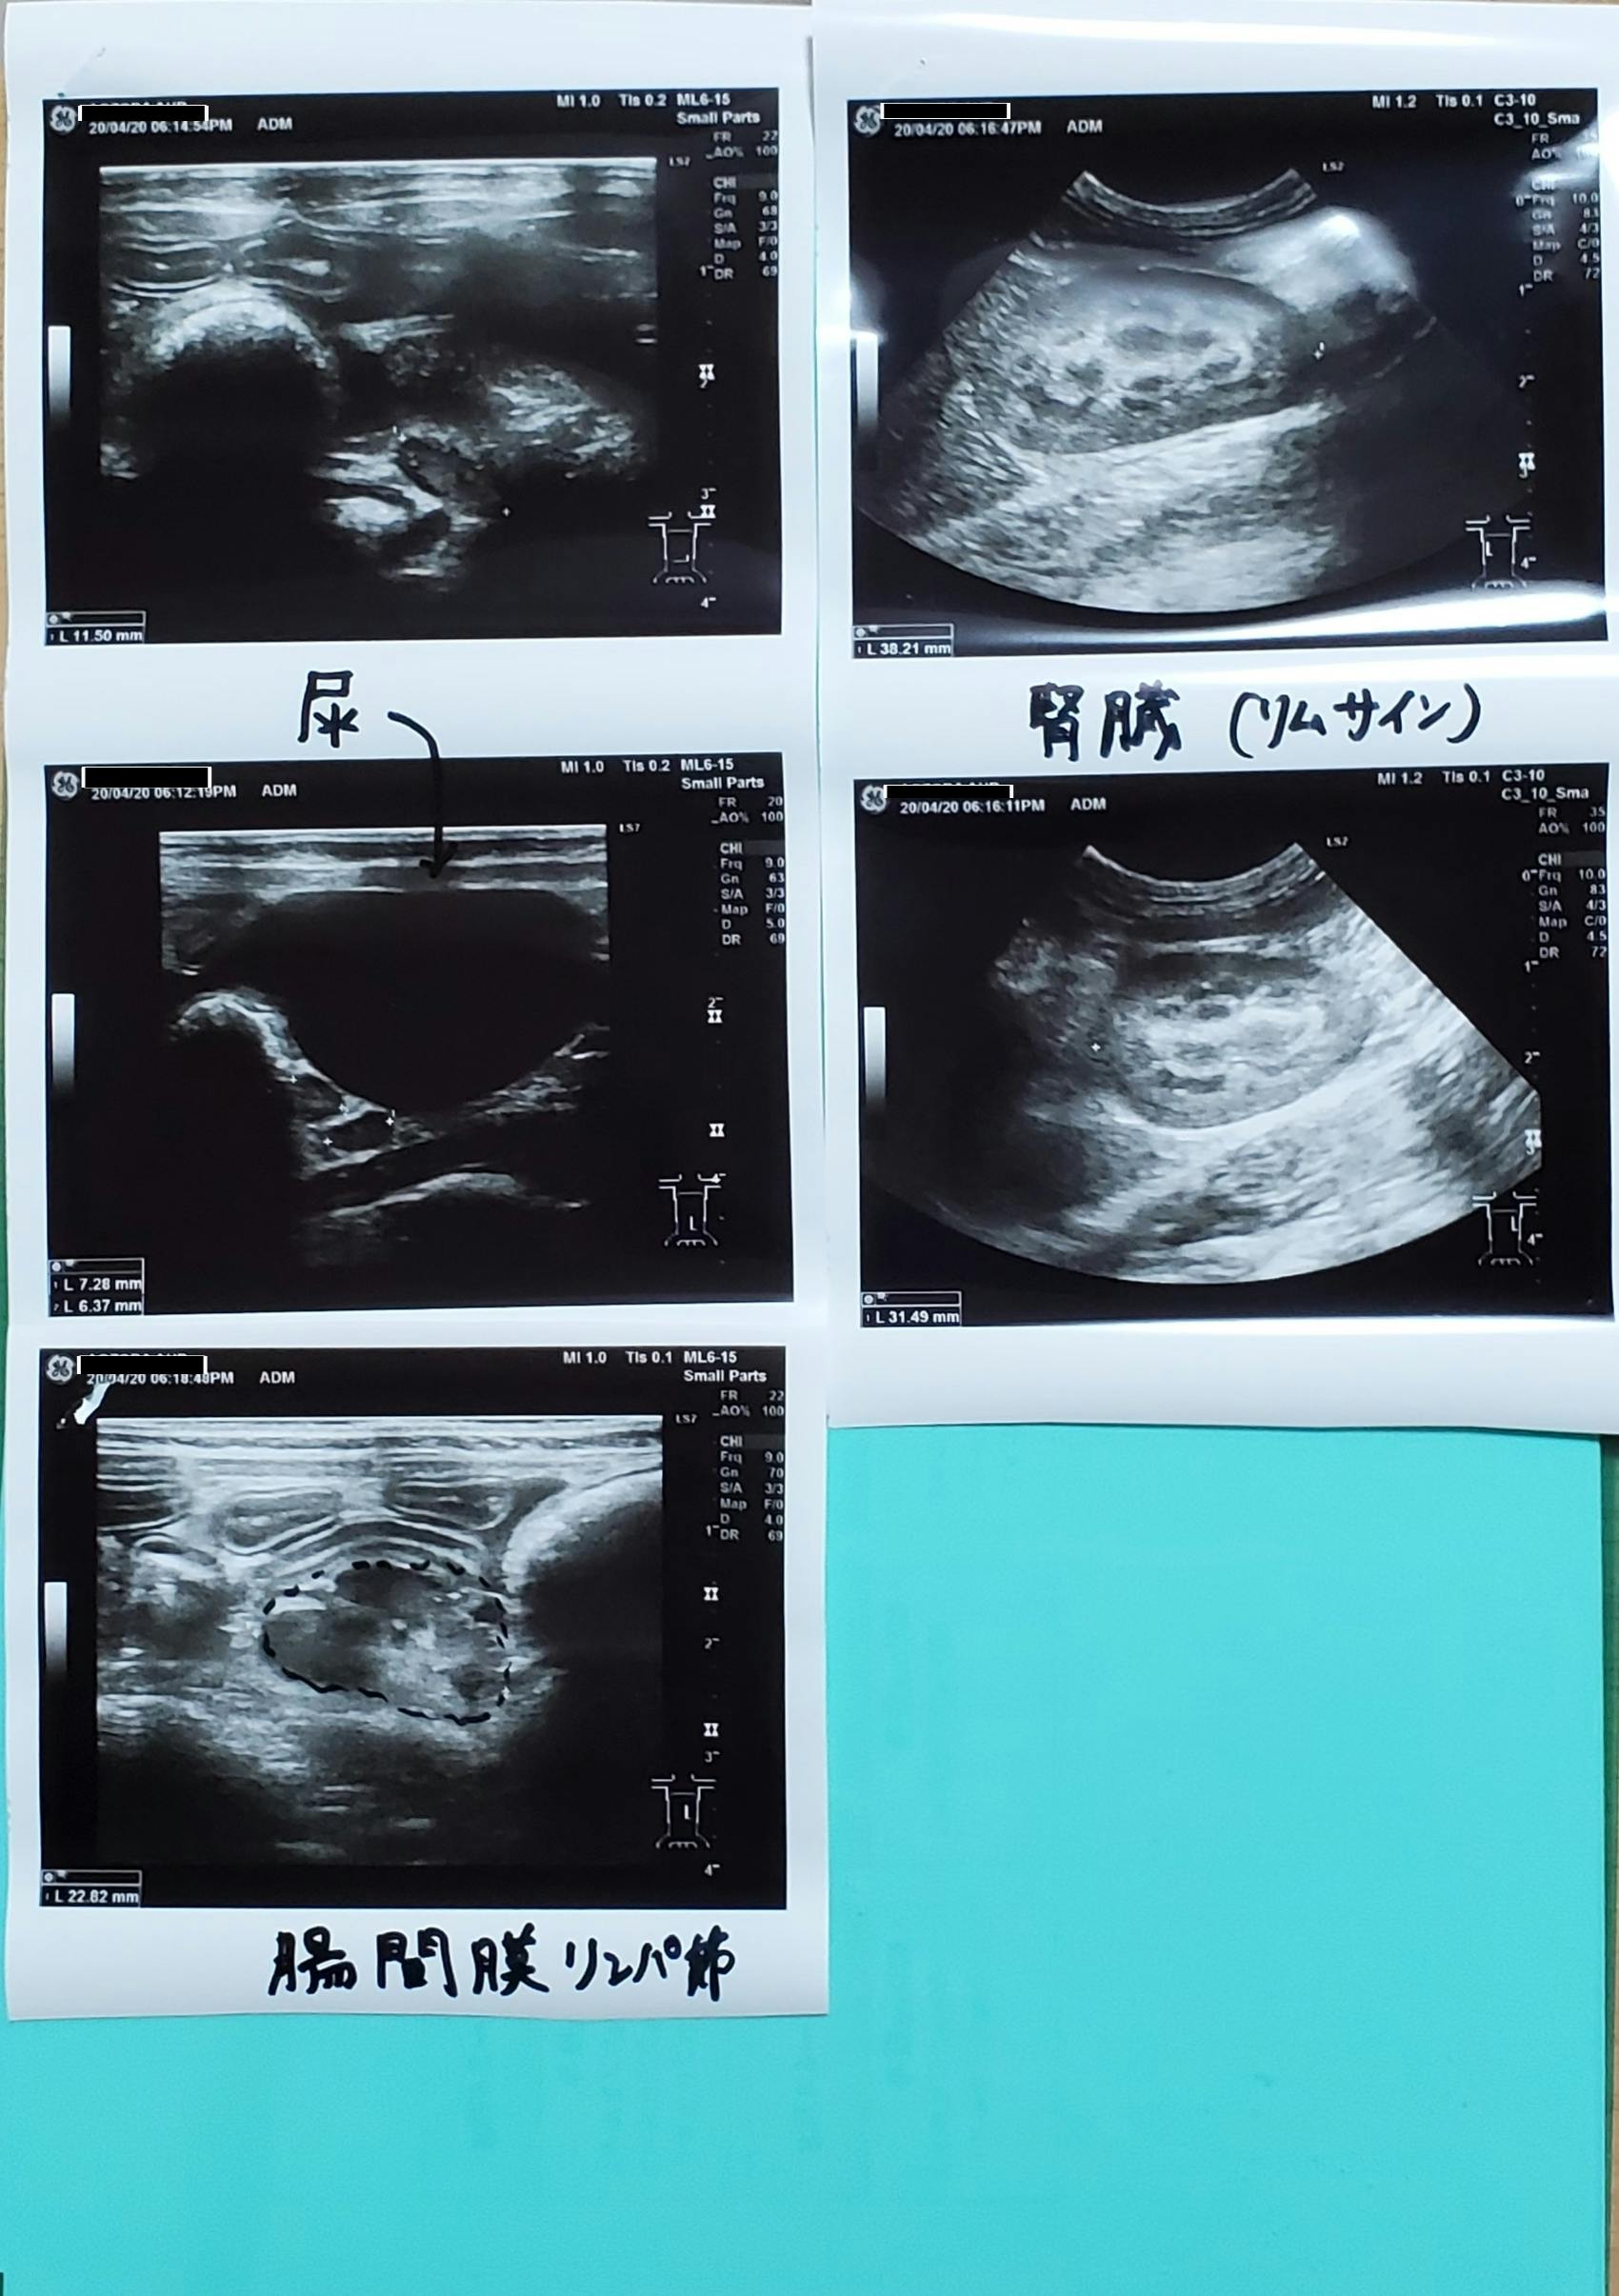

4/11に協力病院へ行き、また痛く辛い検査をし、こちらの協力病院でFIPの中でも稀なウェットとドライの混合タイプ(中期)と診断されました。

腹水がたまっていてエコー画像診断では

膀胱の近くに4cm大の肉芽腫がみつかり

40.1℃の熱と黄疸、重度の貧血もあり

強い炎症の数値2000以上出ているとのこと。

すぐに腹水を抜いて肉芽腫の細胞を採取しできる限りの検査をしていただきました。

※細胞診の結果

腹水=無菌性慢性活動型化膿性炎症。

腫瘤=化膿性肉芽腫

腸間膜リンパ節の腫れ

腎臓(リムサイン)もみられるそうです。

コロナ陽性と出ていることからFIPによるものということでした。